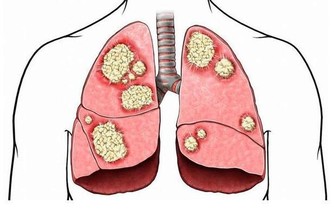

在一年四季之中,氣溫、氣壓、氣流、氣濕等氣象要素最為變化無常的季節是春季。由於氣象要素的多變,在春天常引起許多疾病的複發或增患新病。立春的多發病有肺炎、肝炎、流腦、麻疹、腮腺炎、過敏性哮喘、心肌梗塞、精神病等。因此對於有肝炎、過敏性哮喘、心肌梗塞等患者要特別注意調養預防。